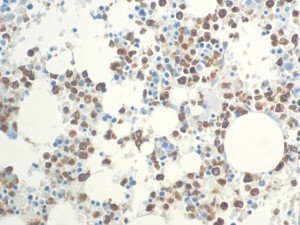

It is the ICU physician who is most likely to witness one of the deadliest manifestations of the abnormal immunological response, the cytokine storm syndrome (CSS). This response is also referred to by some as the cytokine release syndrome (CRS). CSS is characterized by continuous activation and expansion of macrophage and lymphocyte populations, which secrete large amounts of cytokines, causing the cytokine storm. This massive cytokine release is akin to hemophagocytic lymphohistiocytosis (HLH) disease, a syndrome characterized by initial unchecked and persistent activation of cytotoxic T lymphocytes and NK cells.

Clinical and laboratory manifestations of HLH include fever, enlarged liver and/or spleen, neurologic dysfunction, coagulopathy, liver dysfunction, cytopenias (i.e., low levels of erythrocytes, leukocytes, and/or platelets), hypertriglyceridemia, hyperferritinemia, hemophagocytosis, and eventually diminished NK cell activity as the immune system becomes progressively paralyzed. HLH can be familial (primary HLH) or secondary to another disease process (sHLH), such as rheumatic disease, in which it is referred to as macrophage activation syndrome (MAS, characterized by elevated ferritin).